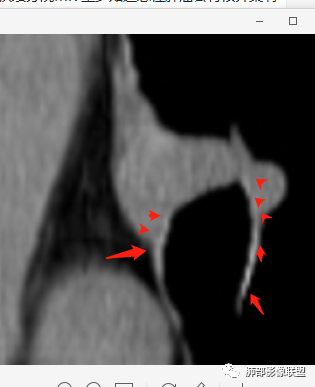

南边:

南边:高密度软骨在这两点上停了

南边:挤过去了,说明是从软骨间过去的

尘缘:@Shelia,部分是向前推,部分是向后推的。这个地方应该还有向后推的;肿物是从向前推与向后推这个间隙跨软骨的。

南边:需要用连续的窄窗观察。